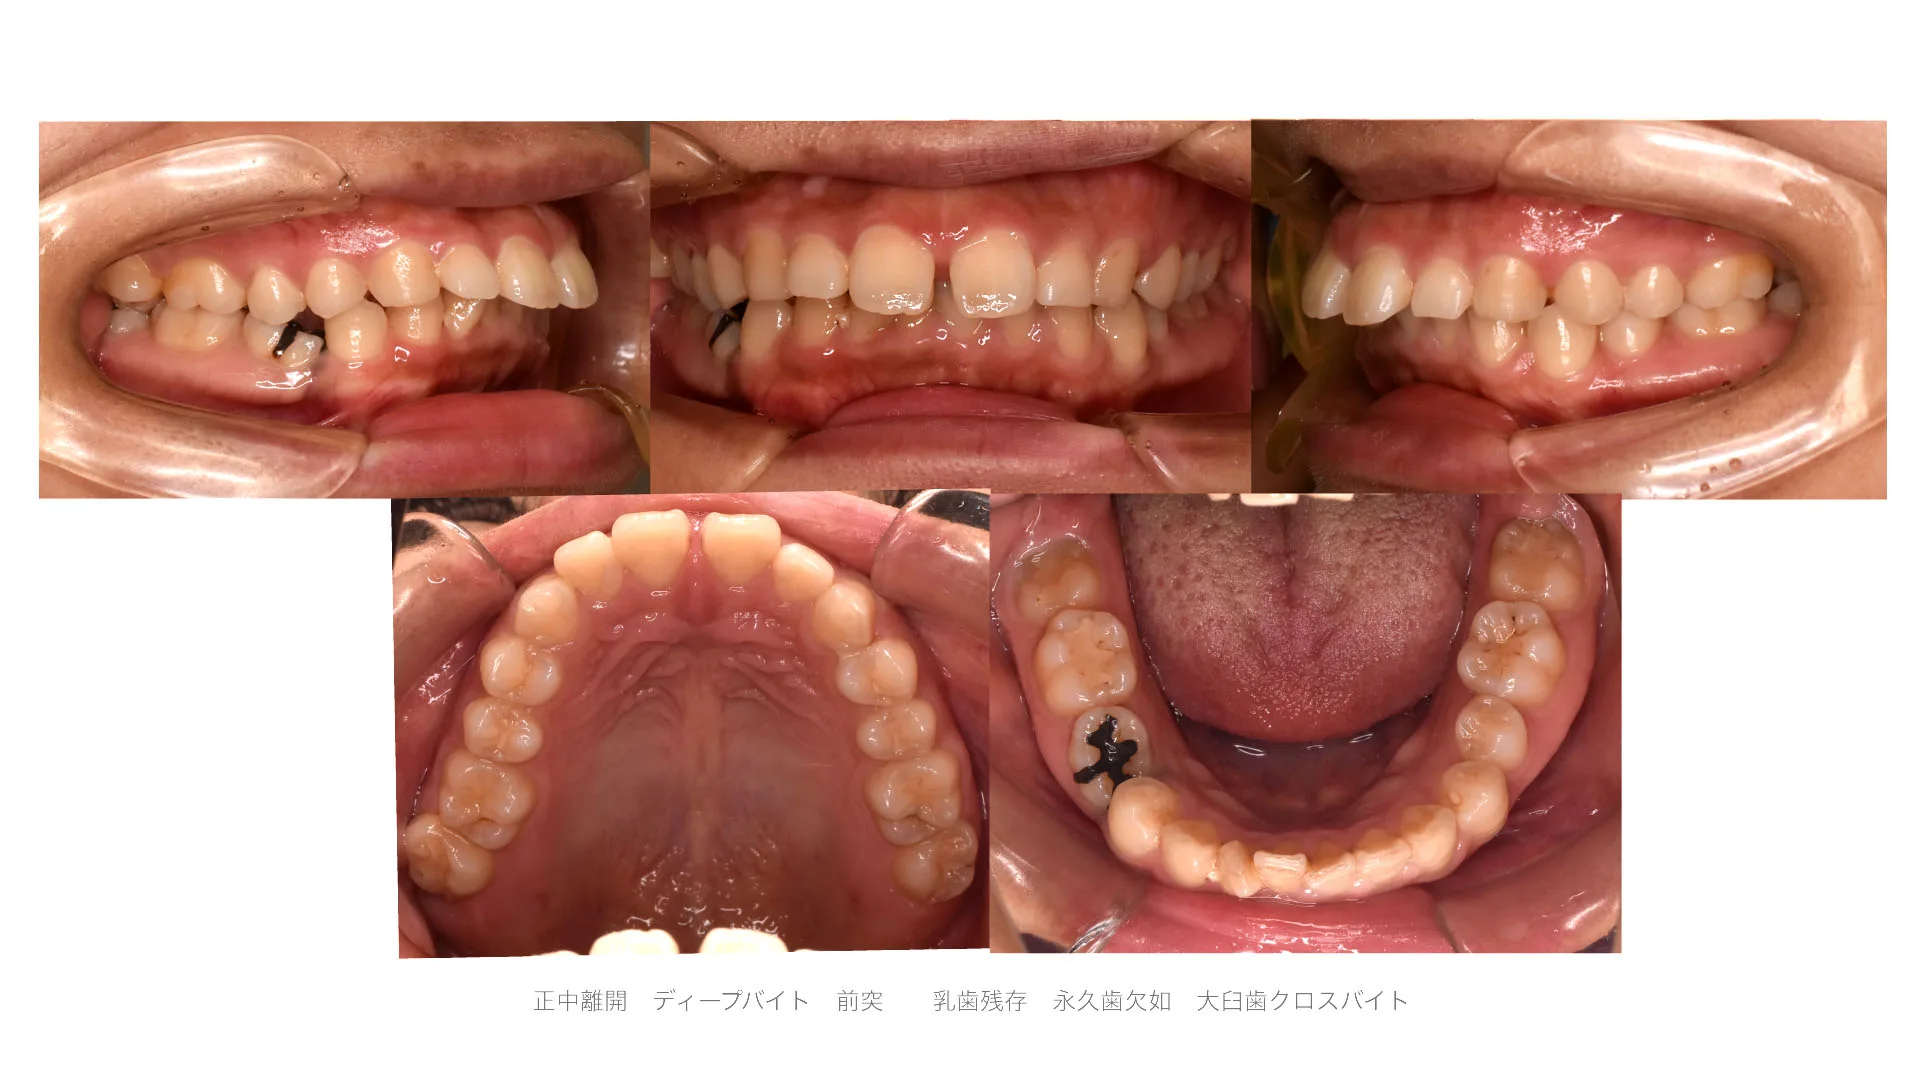

症例 口唇突出、正中離開